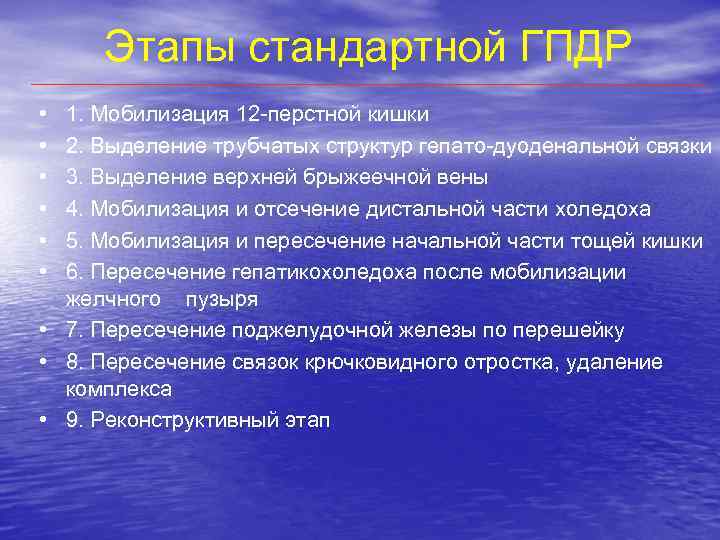

Этапы стандартной ГПДР • • • 1. Мобилизация 12 -перстной кишки 2. Выделение трубчатых структур гепато-дуоденальной связки 3. Выделение верхней брыжеечной вены 4. Мобилизация и отсечение дистальной части холедоха 5. Мобилизация и пересечение начальной части тощей кишки 6. Пересечение гепатикохоледоха после мобилизации желчного пузыря • 7. Пересечение поджелудочной железы по перешейку • 8. Пересечение связок крючковидного отростка, удаление комплекса • 9. Реконструктивный этап